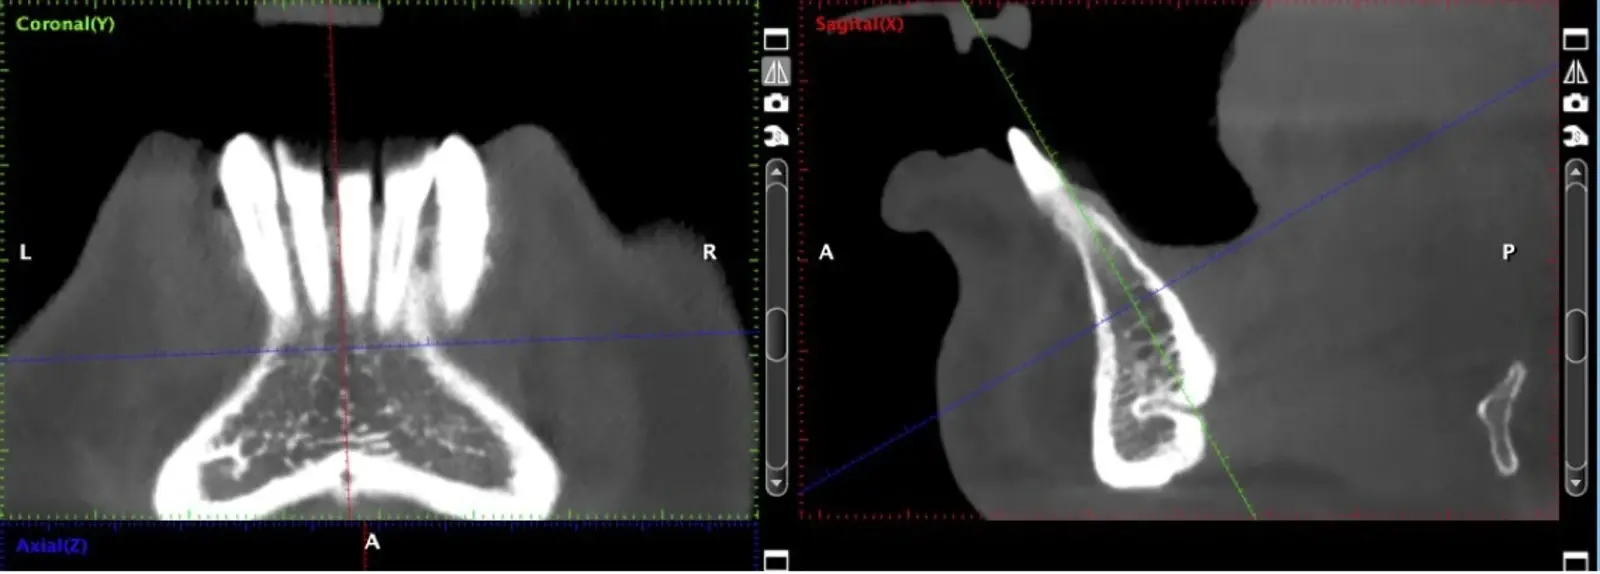

La literatura menciona varias complicaciones relacionadas con la extracción de injertos óseos, la mayoría de ellas asociadas con el corte y la manipulación de zonas próximas a estructuras de riesgo; entre las más comunes, las lesiones nerviosas con consecuente adormecimiento, molestias postoperatorias (abertura bucal limitada, sangrado, hinchazón y dolor) y problemas estéticos (cambios en el contorno del área donadora o recesión de tejidos blandos).10 Aunque los injertos de rama pueden presentar menos molestias postoperatorias, tienen un acceso quirúrgico limitado debido a la apertura bucal y el peligro potencial de lesionar el paquete vásculo-nervioso cercano.11

El uso de vibraciones ultrasónicas se introdujo por primera vez hace dos décadas para superar las limitaciones de la instrumentación tradicional.12,13 Altiparmak y cols.14 reportaron en su estudio que la cirugía piezoeléctrica redujo significativamente la incidencia de alteraciones sensoriales tanto de la piel como de la mucosa oral, y redujo también el daño pulpar en los dientes adyacentes, sobre todo en los injertos sinfisiarios.

La osteotomía con insertos de piezoeléctrico nos permite un corte más definido con menor pérdida de hueso residual, ya que los insertos son extremadamente finos.